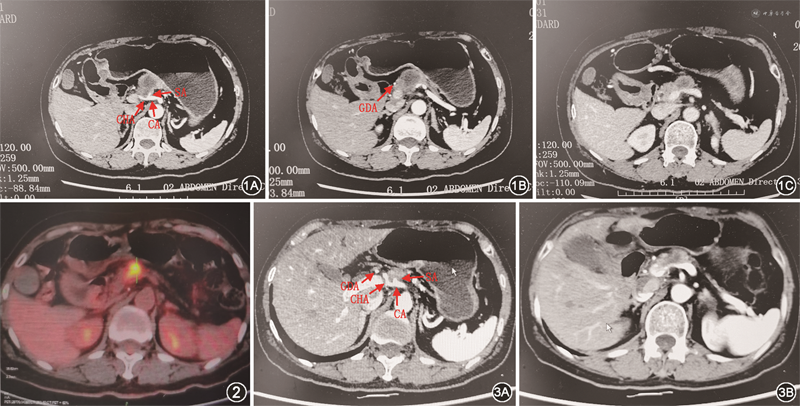

依据术前影像学检查结果,由多学科团队(multidisciplinary team,MDT)评估肿瘤的可切除性。MDT认为肿瘤累及腹腔干、肝总动脉、脾动脉、胃左动脉,紧贴胃十二指肠动脉,侵犯脾静脉汇入门静脉处,未累及肠系膜上动脉(图1)。根据指南推荐意见[1],该患者为交界可切除胰腺癌,肿瘤与胃十二指肠动脉紧贴,直接行改良Appleby手术难以获得阴性切缘。与患者及其家属充分沟通后,行改良FOLFIRINOX方案(氟尿嘧啶+亚叶酸钙+奥沙利铂+伊利替康)的新辅助化疗,3个疗程后重新评估,各项肿瘤指标不同程度降低,CA19-9降至272.5 U/ml;但肿瘤体积缩小不明显,大小36 mm×29 mm;后续给予序贯长程放化疗(2 Gy/次,25次;吉西他滨),血液肿瘤指标均明显下降,CA19-9 48.4 U/ml,肿瘤缩小至27 mm×14 mm;后续再予吉西他滨+白蛋白紫杉醇(AG方案)3个疗程,期间给予替雷利珠单抗(200 mg/3周×5次),血液肿瘤指标继续下降,CA19-9 13.7 U/ml,肿瘤继续缩小至13 mm×9 mm。共7个多月新辅助治疗后,血液肿瘤指标基本降至正常范围,肿瘤显著缩小。术前PET-CT检查结果提示肿瘤仍有活性,但无远处转移(图2)。MDT再次评估肿瘤的可切除性,基于以下几点决定行改良Appleby手术+部分门静脉置换术:(1)肿瘤未累及胰头,无远处转移;(2)肿瘤侵犯腹腔干、肝总动脉、脾动脉近端和胃左动脉,但肝固有动脉、肠系膜上动脉未累及;(3)腹腔干根部未见肿瘤浸润;(4)新辅助治疗后肿瘤明显缩小,胃十二指肠动脉远离肿瘤,未被侵及;(5)肿瘤仍侵犯脾静脉汇入门静脉处;(6)上腹部未见动脉走行变异(图3)。